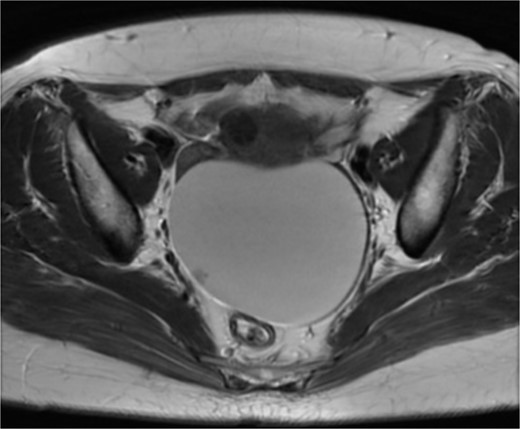

On admission, the patient was found to have a soft tumor, 10 cm in size, in her lower abdomen. She didn’t feel any tenderness at the site of the tumor. Abdominal ultrasonography showed a cystic mass with a small solid portion with a clear margin. Her serum levels of CA125, CA19-9, and carcinoembryonic antigen (CEA) were within normal limits. Computed tomography (CT) scan revealed a 10 cm sized cystic mass (Fig. 1). Magnetic resonance imaging (MRI) also revealed a 10 cm sized cystic mass with a solid part in the pelvis (Fig. 2).

Pelvic computed tomography image: A large mass occupying the pelvis which is a 10 cm sized cystic mass.